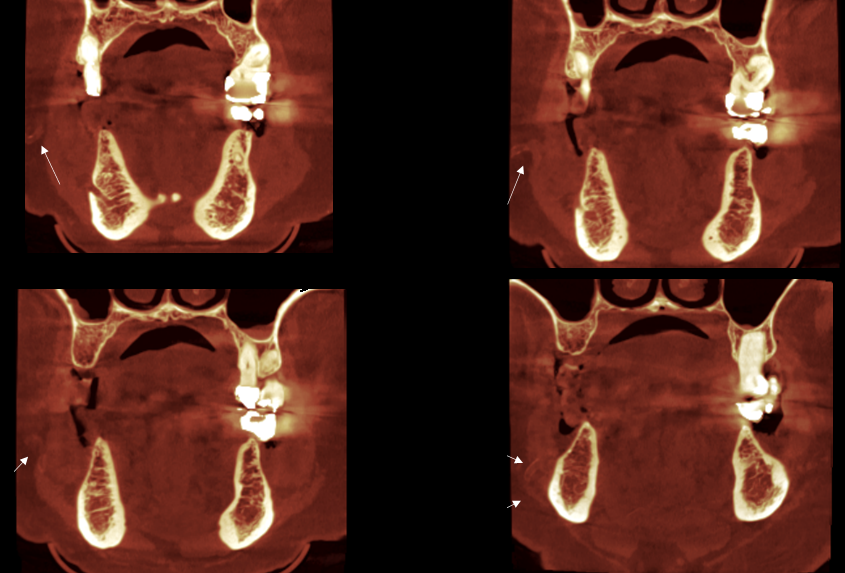

En la reconstrucción 3D de tejidos blandos se observa el recorrido de la arteria facial mineralizada (Figura 4)

RECONSTRUCCIÓN 3D